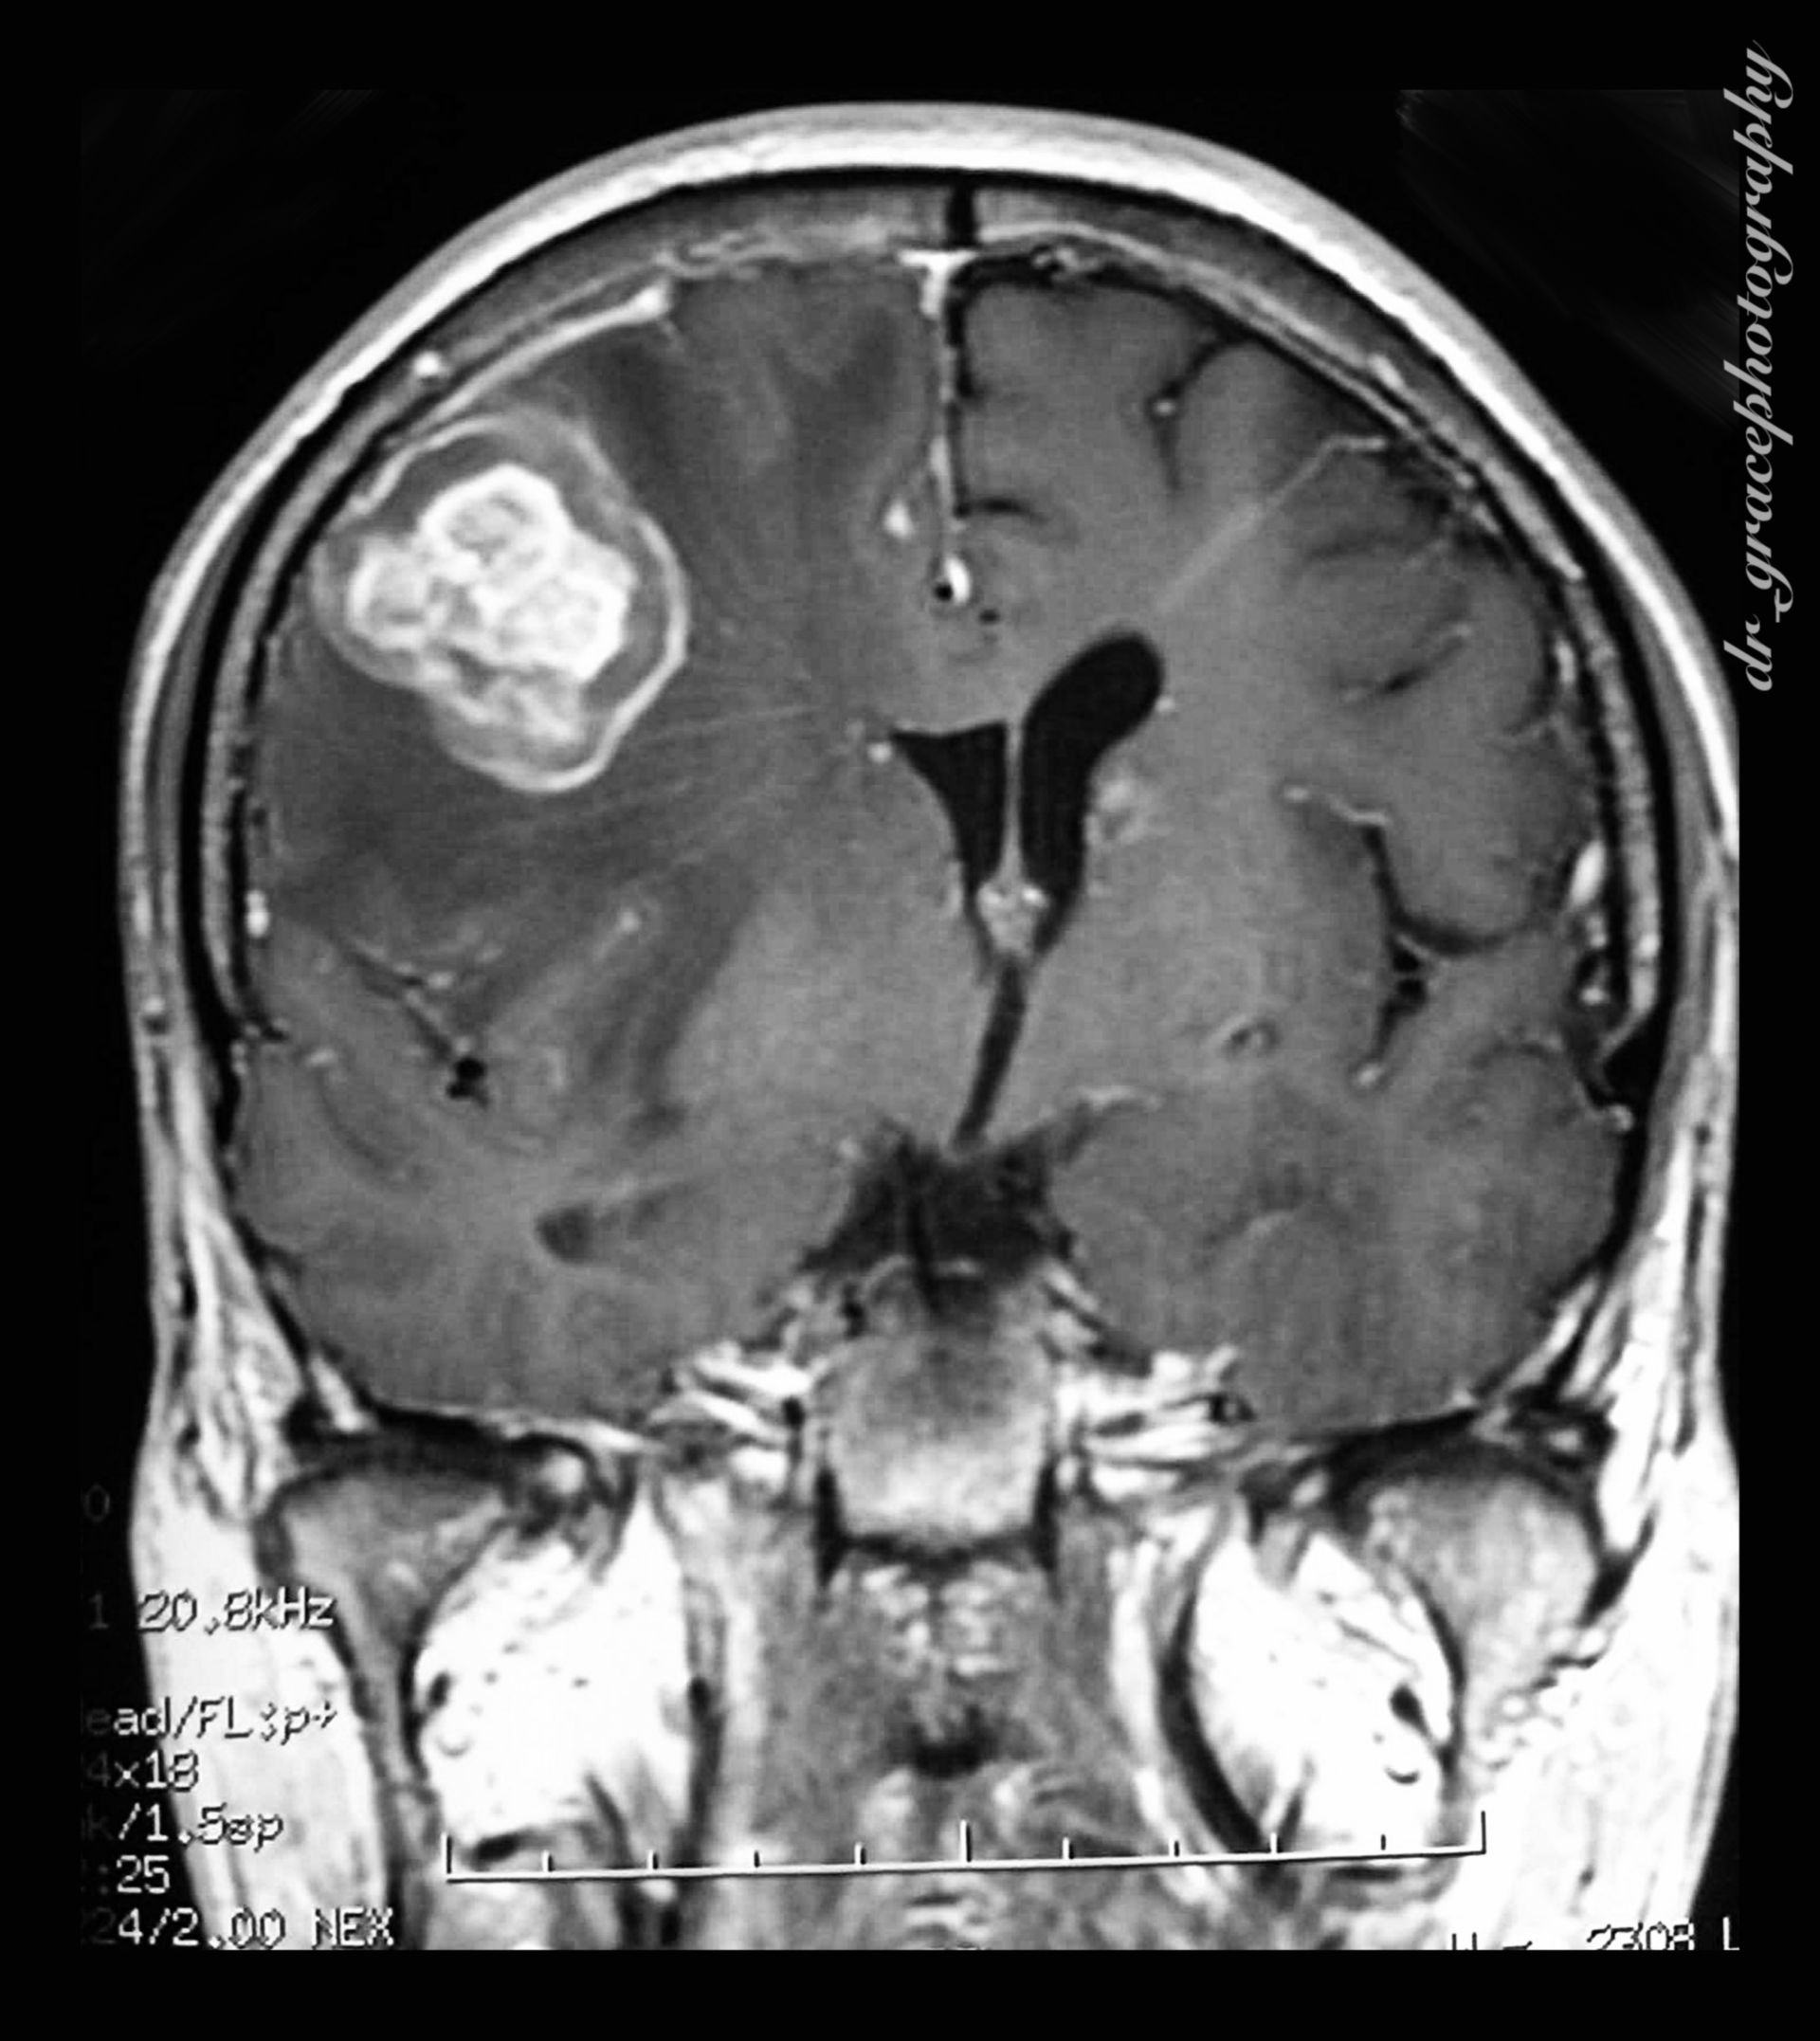

MRT Bild, könnte das ein Tumor sein? Kennt sich jemand damit aus? Könnte die helle Fläche ein … Myokarditis (MRT) – DocCheck

?wer kann helfen?ist in diesen MRT ein Tumor sichtbar? MRT abdomen – DocCheck

MRT Bilder-Hubbel-??? Hilfe (Kopf) รีวิว คอนโด Niche MONO อิสรภาพ เพียง 200 เมตร จาก MRT อิสรภาพ ใกล้ รพ.ศิริราช

Glioblastom in der MRT,T1-gewichtet mit Kontrastmittel, sagitaler Schnitt aus dem KGU | Kampf … MRT eines Bandscheibenvorfalls an der LWS – Lizenzfreies Bild – #15202613 | Bildagentur PantherMedia